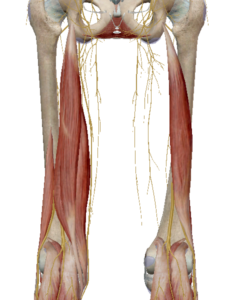

(13) 슬굴곡근